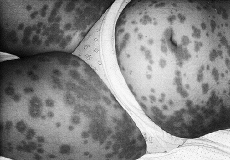

Mujer de 25 años, sin antecedentes personales de interés, que había tenido un embarazo 5 años antes sin ninguna complicación cutánea u obstétrica y que en el segundo trimestre del actual embarazo, a las 20 semanas, comenzó con una erupción a nivel umbilical consistente en placas intensamente pruriginosas con algún elemento papuloso en brazos y resto del tronco. Fue tratada inicialmente con antihistamínicos y corticoterapia tópica durante una semana a pesar de lo cual el proceso cutáneo se extendió hasta ocupar casi toda la superficie del tronco, muslos y brazos, en forma de placas que llegaban a formar una superficie vesiculosa (Fig. 1). Se realizó una biopsia de una de las placas, viéndose en la tinción con hematoxilina eosina edema e infiltración por linfocitos y abundantes eosinófilos; la inmunofluorescencia directa mostró C3 lineal en la unión dermoepidérmica sin detectarse IgG. No se pudo realizar inmnunofluorescencia indirecta. Se instauró tratamiento con 30 mg/día de prednisona, aumentando a 40 mg y posteriormente a 50 mg/día ante la la falta de respuesta. Con esta última dosis el proceso cutáneo se estabilizó parcialmente, pero al intentar descender la dosis recidivaba y obligaba a mantener esa pauta.

FIG. 1.--Lesiones en placas papuloampollosas en tronco y extremidades.